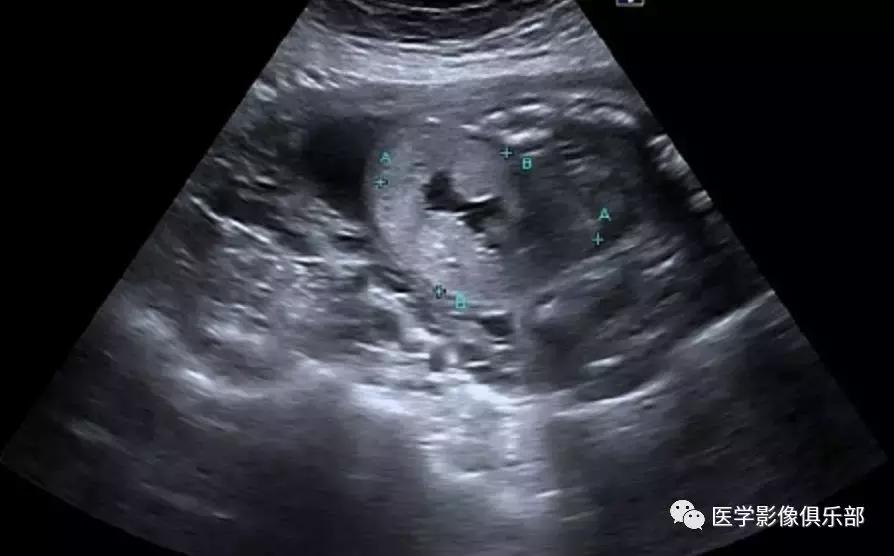

[病例举例]:常规产科超声显示胎龄26周胎儿畸形。

胎儿超声显示双肾明显增大,回声增强,羊水量较少。